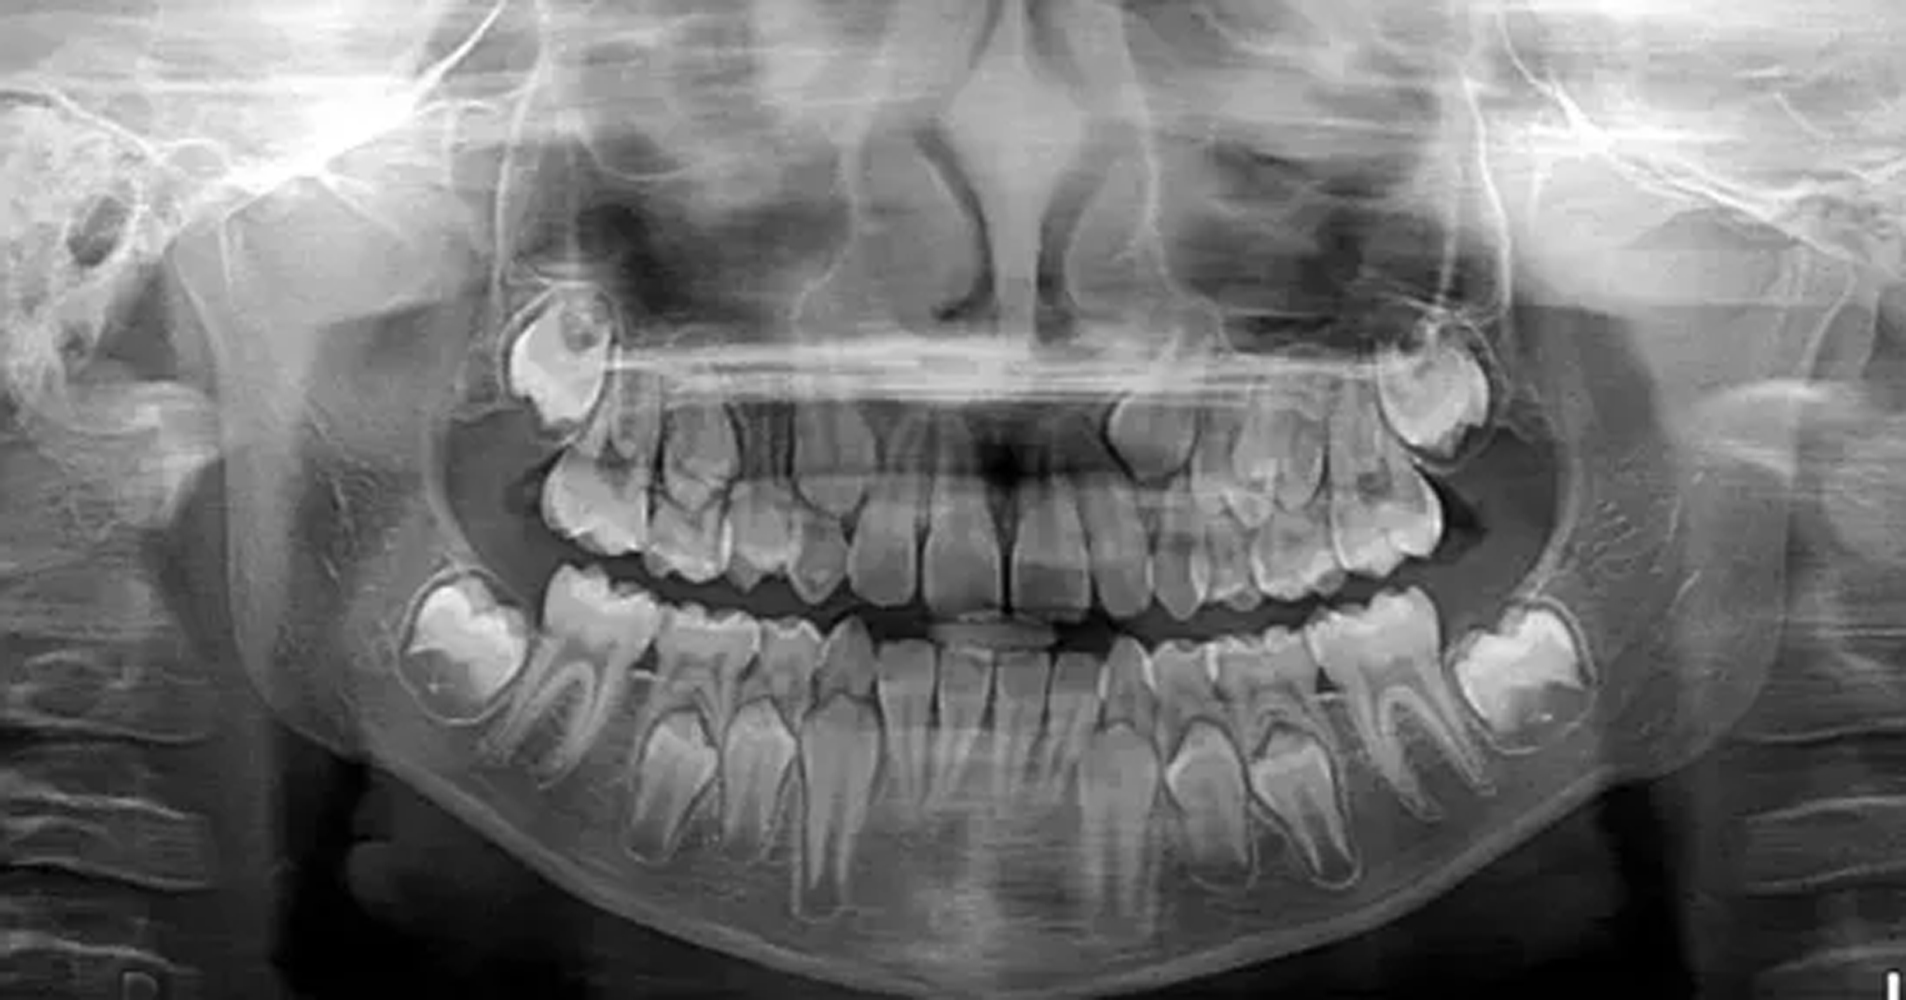

Among clear evidence that ICE and Homeland is violating their own mandate NOT to use wisdom teeth and bone analysis, it is still a large money-maker for dentists when they are hired by ICE and Homeland to put children into adult detention. Here’s a quote from this LA Times article.

“In a report for an attorney this year opposing the use of third molar estimates, Dr. Mike Bowers, a dentist who practices forensic odontology, stated that “dental aging should be considered an indicator of the biological maturity of a growing child. It was not developed to be used for individual age identification.”